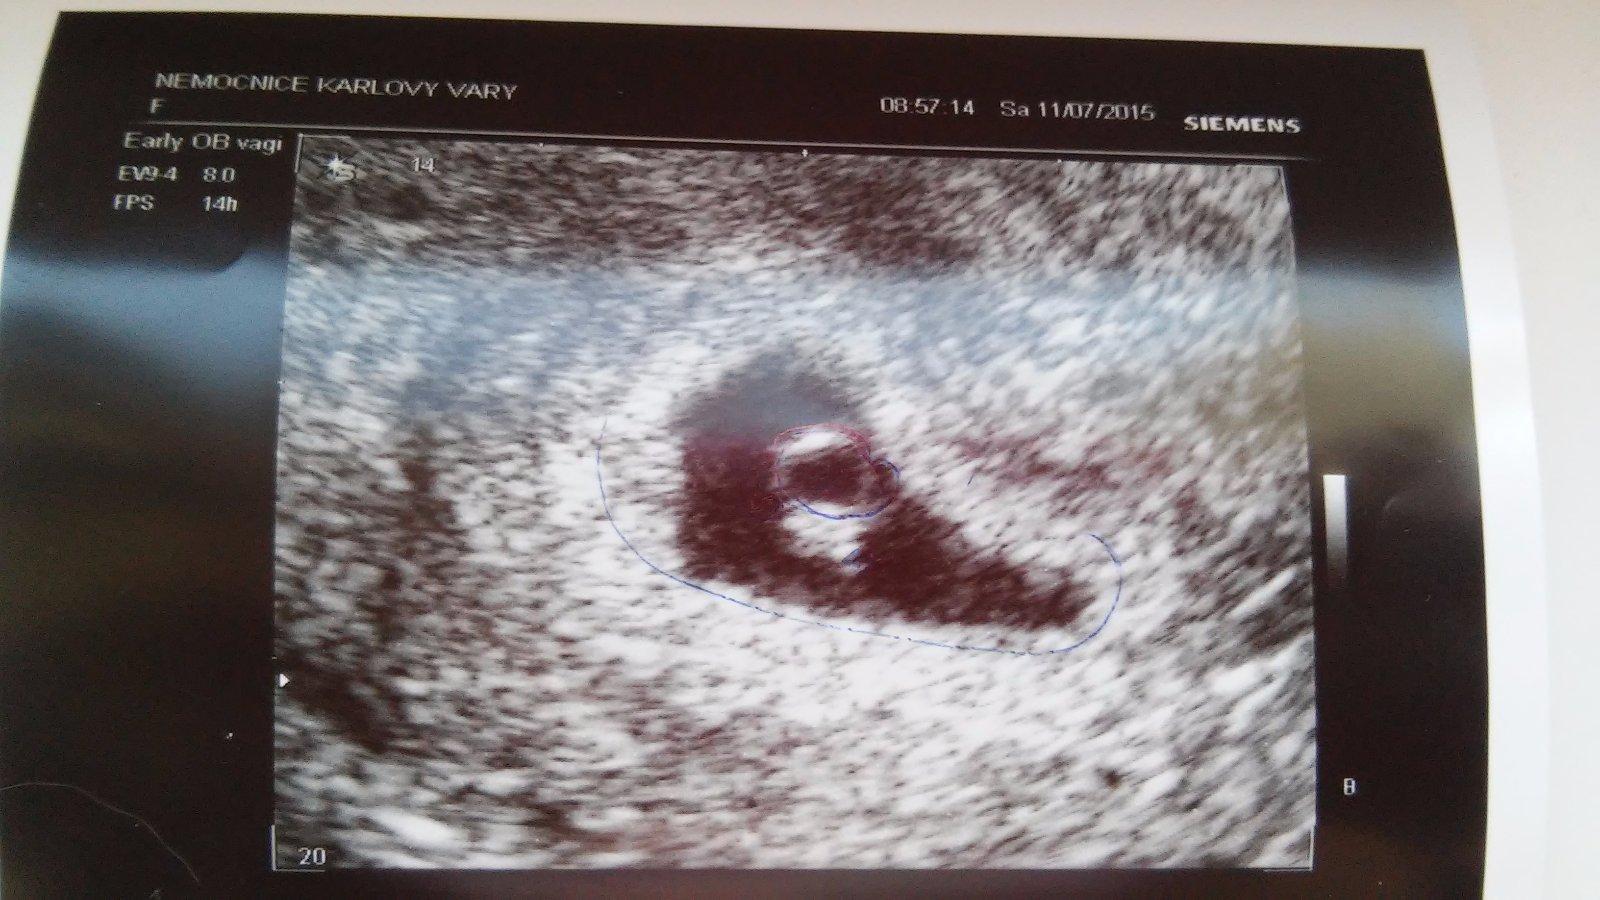

Dnešní ráno čekalo i mě velmi nemilé překvapení ☹ večer jsme se pohádali s manželem. Ráno vstanu, šla jsem do koupelny a brutálně jsem krvácela. Vypadl ze mě i obrovský cucek, tak jsem myslela, že je to mimi. No jeli jsme rovnou na pohotovost. Doktor mě vyšetřil, udělal USG a co se nestalo. Naše embryjko má přesně 3mm a srdíčko mu bije jak o závod. Jsem ještě pořád v hrozným šoku a nejde mi přestat brečet. 🙂 Mám o něj hrozný strach 😖 Takže hrozný zážitek, se šťastným koncem 😀

@briketaaaa to mě dostalo a brečím teď taky. Je to bojovníček a jen tak se nepustí 🙂 Je dobře, že je v pořádku a doma se teď nehádejte! Krásná fotka 🙂